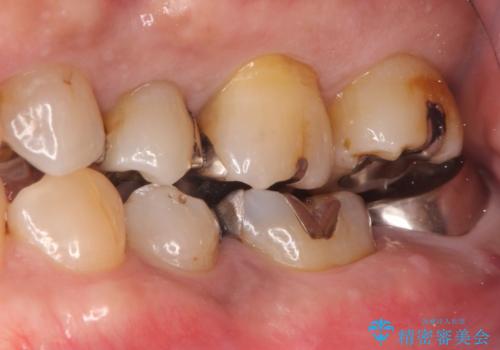

- 他院で治療したが、痛みが続いていることを主訴に来院されました。

痛みの原因歯を特定し、根管治療を行い、オールセラミッククラウンにて咬合回復しております。

根管治療は林先生に依頼しております。